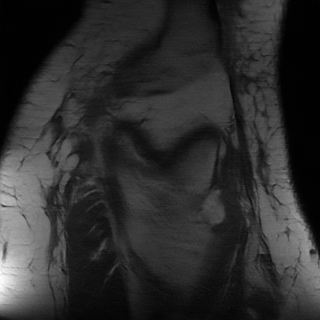

We compared all models on the validation and test set using the metrics suggested in Zbontar et al. [28]. A summary of this comparison can be found in table 2. Both i-RIM models consistently outperform the baselines. At the time of this writing, all three models sit on top of the challenge’s Single-Coil leaderboard.222http://fastmri.org/leaderboards, Team Name: NeurIPS_Anon; Model aliases: RIM - model_a, i-RIM 2D - model_b, i-RIM 3D - model_c. See Supplement for screenshot. The i-RIM 3D shows almost as good performance as it’s 2D counterpart and we believe that with more engineering and longer training it has the potential to outperform the 2D model. A qualitative assessment of reconstructions of a single slice can be found in figure 3. We chose this slice because it contains a lot of details which emphasize the differences across models.

Refer to caption

(a) Target Image

(b) U-Net 4x

(c) RIM 4x

(d) i-RIM 4x

(e) i-RIM 3D 4x

(f) Target Image

(g) U-Net 8x

(h) RIM 8x

(i) i-RIM 8x

(j) i-RIM 3D 8x

Figure 3: Reconstructions of a central slice in volume ’file1001458.h5’ from the validation set. Top: 4x acceleration. Bottom: 8x acceleration. Zoom in for better viewing experience.